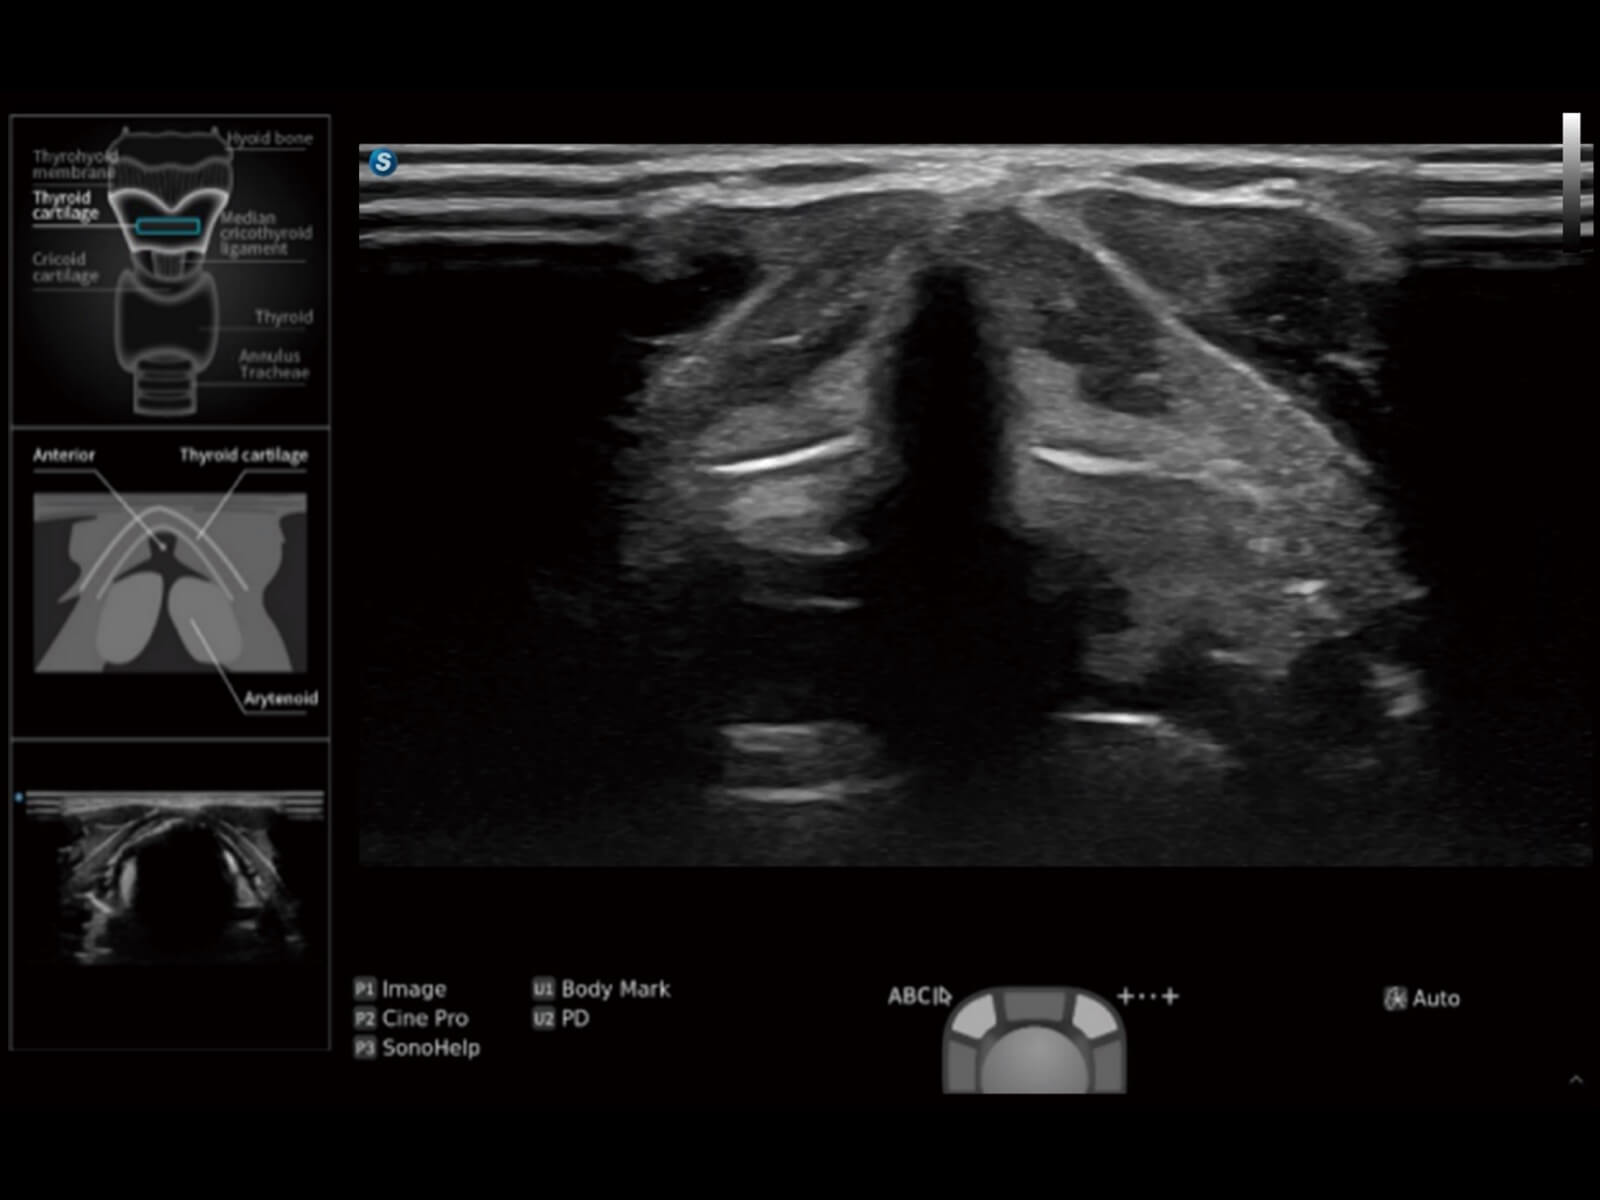

重症监护

麻醉